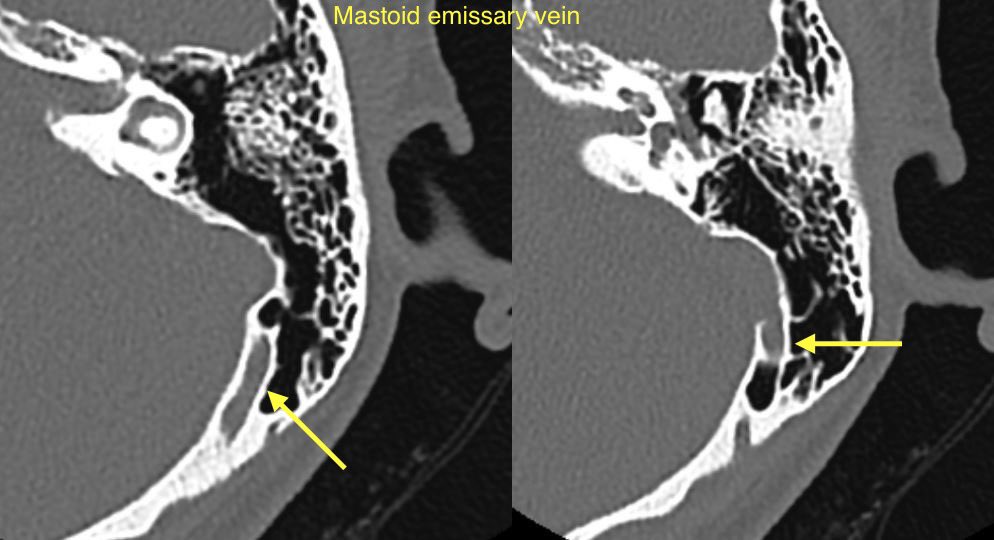

🔷EMISSARY VEIN ANOMALIES AND VARIANTS

1️⃣Mastoid emissary veins

🔹Mastoid emissary veins (connect posterior auricular or occipital veins with the sigmoid sinus). These are common & usually incidental findings though have been associated with PT